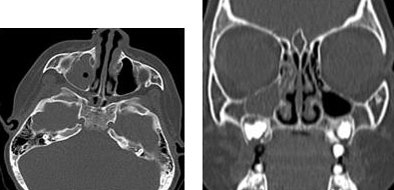

| Axial (left) and coronal (right) MDCT images of a 12-year-old with calcaneous osteoid osteoma show bone detail. |